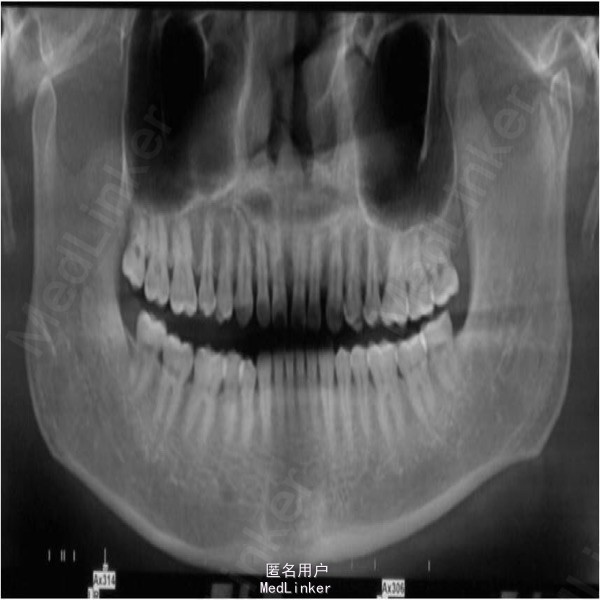

颏部可见擦伤,其余部位未见明显外伤。曲面断层和CT提示,左侧髁突骨质连续性中断

左侧髁突骨折 全麻下切开复位内固定